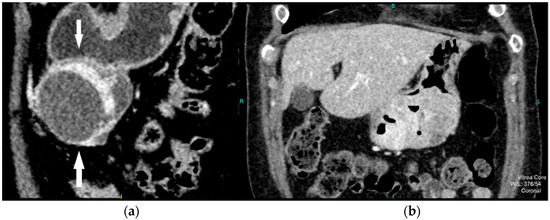

CT imaging features were analyzed as follows: maximal diameter in the axial slice and tumor structure, which was classified into cystic and solid/necrotic. The shape was depicted as regular or irregular. Tumor localization considered the body of the stomach, antrum or pyloric region. Mucosa was observed in two ways: intact/continuous or disrupted. Growth patterns were categorized as exophytic/mixed or endophytic. The degrees of enhancement of the solid part of tumor tissue were divided into weak, moderate or obvious enhancements. The presence of enlarged feeding or draining vessels (EFDV) was also recorded, as was the presence of metastasis in liver and other organs ( Figure 1, Figure 2 and Figure 3).

Figure 1. Contrast enhanced computed tomography of the abdomen, axial view, demonstrates low grade GIST (white arrow) in a 54-year old male patient as submucosal, with a round lesion with endophytic growth in the subcardial region of gastric body. The tumor has an approximate diameter of 45 mm, a solid structure with low post-contrast opacification, covered by an intact mucosa.